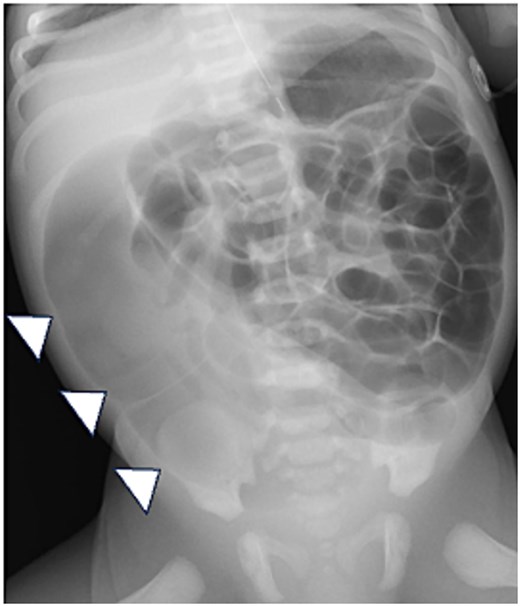

Abdominal X-ray. The X-ray shows diffuse intestinal and colonic distension, especially a dilated sigmoid colon (arrowheads).